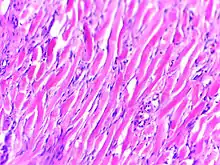

Pathology

Histologically, keloids are fibrotic tumors characterized by a collection of atypical fibroblasts with excessive deposition of extracellular matrix components, especially collagen, fibronectin, elastin, and proteoglycans. Generally, they contain relatively acellular centers and thick, abundant collagen bundles that form nodules in the deep dermal portion of the lesion. Keloids present a therapeutic challenge that must be addressed, as these lesions can cause significant pain, pruritus (itching), and physical disfigurement. They may not improve in appearance over time and can limit mobility if located over a joint.